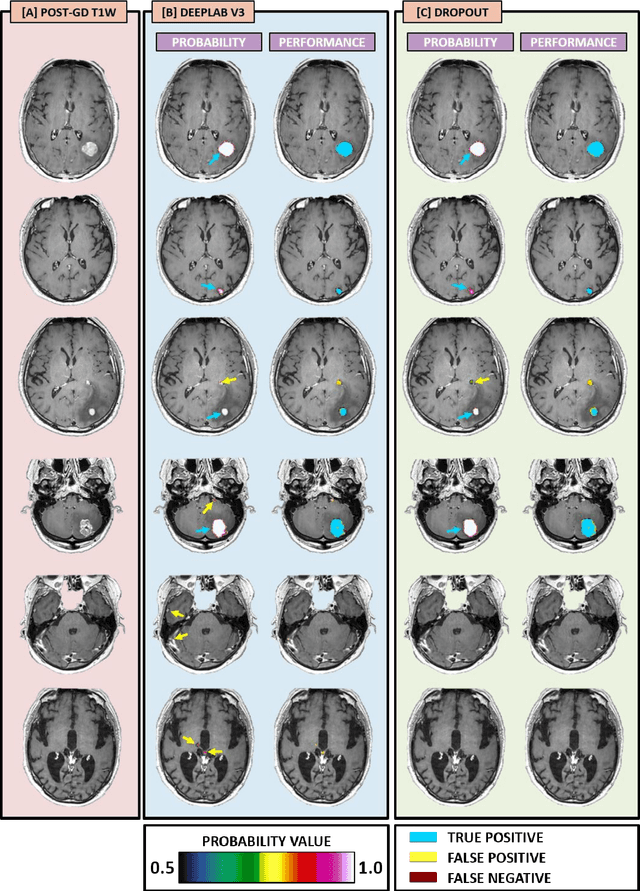

Abstract:The purpose was to assess the clinical value of a novel DropOut model for detecting and segmenting brain metastases, in which a neural network is trained on four distinct MRI sequences using an input dropout layer, thus simulating the scenario of missing MRI data by training on the full set and all possible subsets of the input data. This retrospective, multi-center study, evaluated 165 patients with brain metastases. A deep learning based segmentation model for automatic segmentation of brain metastases, named DropOut, was trained on multi-sequence MRI from 100 patients, and validated/tested on 10/55 patients. The segmentation results were compared with the performance of a state-of-the-art DeepLabV3 model. The MR sequences in the training set included pre- and post-gadolinium (Gd) T1-weighted 3D fast spin echo, post-Gd T1-weighted inversion recovery (IR) prepped fast spoiled gradient echo, and 3D fluid attenuated inversion recovery (FLAIR), whereas the test set did not include the IR prepped image-series. The ground truth were established by experienced neuroradiologists. The results were evaluated using precision, recall, Dice score, and receiver operating characteristics (ROC) curve statistics, while the Wilcoxon rank sum test was used to compare the performance of the two neural networks. The area under the ROC curve (AUC), averaged across all test cases, was 0.989+-0.029 for the DropOut model and 0.989+-0.023 for the DeepLabV3 model (p=0.62). The DropOut model showed a significantly higher Dice score compared to the DeepLabV3 model (0.795+-0.105 vs. 0.774+-0.104, p=0.017), and a significantly lower average false positive rate of 3.6/patient vs. 7.0/patient (p<0.001) using a 10mm3 lesion-size limit. The DropOut model may facilitate accurate detection and segmentation of brain metastases on a multi-center basis, even when the test cohort is missing MRI input data.

Abstract:Magnetic resonance (MR) imaging is an essential diagnostic tool in clinical medicine. Recently, a variety of deep learning methods have been applied to segmentation tasks in medical images, with promising results for computer-aided diagnosis. For MR images, effectively integrating different pulse sequences is important to optimize performance. However, the best way to integrate different pulse sequences remains unclear. In this study, we evaluate multiple architectural features and characterize their effects in the task of metastasis segmentation. Specifically, we consider (1) different pulse sequence integration schemas, (2) different modes of weight sharing for parallel network branches, and (3) a new approach for enabling robustness to missing pulse sequences. We find that levels of integration and modes of weight sharing that favor low variance work best in our regime of small data (n = 100). By adding an input-level dropout layer, we could preserve the overall performance of these networks while allowing for inference on inputs with missing pulse sequence. We illustrate not only the generalizability of the network but also the utility of this robustness when applying the trained model to data from a different center, which does not use the same pulse sequences. Finally, we apply network visualization methods to better understand which input features are most important for network performance. Together, these results provide a framework for building networks with enhanced robustness to missing data while maintaining comparable performance in medical imaging applications.